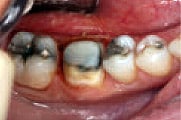

Figure 2

Tooth prep prior

to placement of Protemp™ Crown Temporization Material, buccal

view. |